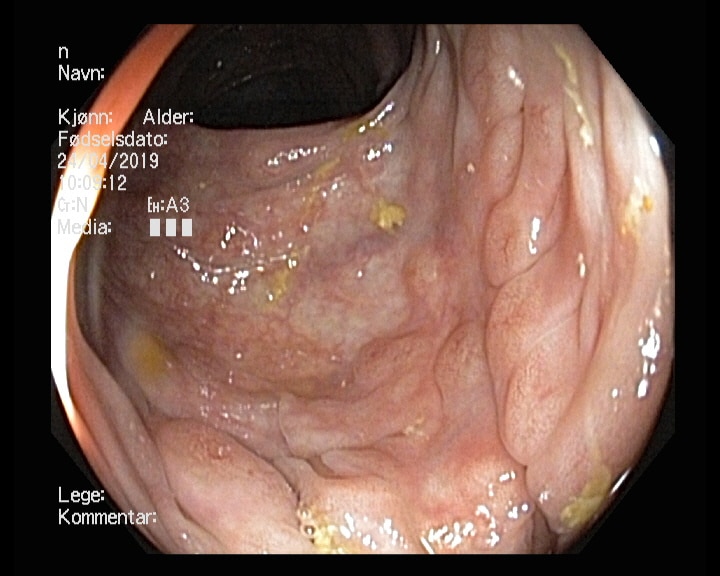

Tidligere frisk mann f.-33 som kom til koloskopi pakkeforløp pga magesmerter, endret avføring, Hb-fall tre enheter og pos hemofec. Trombocytopeni. Bedring etter oppstart PPI. Dag 1 dårlig tømt, kun distal skopi, men funn av stor polypp i venstre colon. Ved gastroskopi ulcerasjoner i tilheling. Dag 2 koloskopi med funn av atypiske polypøse lesjoner i mye av colon, både store og små. Bilde nr. 2 og 3: analt og oralt for sigmoideumvolvulus. Diagnose?